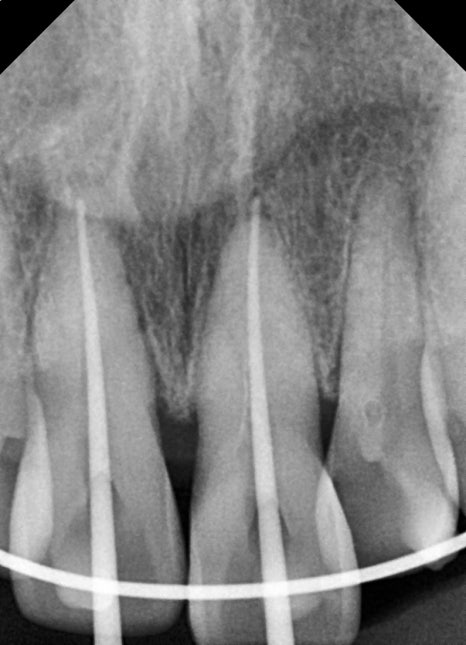

회복 기간 이후 앞니 신경치료까지

강한 충격을 받은 치아는

몇 주~몇 달 뒤 시림, 통증, 변색이 발생할 수 있습니다.

이는 신경 손상 때문입니다.

환자분도 앞니 두 개에서 신경 괴사 가능성이

확인되어 정확한 근관장 측정 후

신경치료가 진행되었습니다.

신경치료가 정확히 이루어지지 않으면 향후

치근단염이나 재신경치료가 필요할 수 있어,

앞니 외상에서는 “지켜보자”보다

적기에 치료하는 것이 안전합니다.